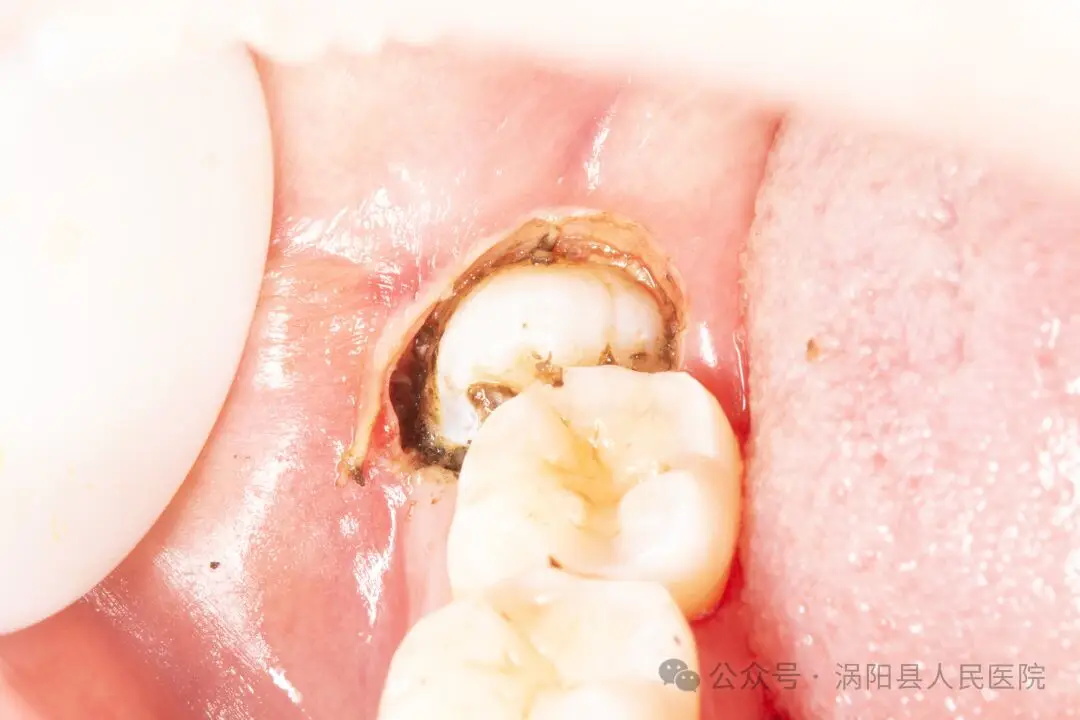

近日,30岁的刘女士因下颌智齿反复发炎至我院就诊,刘女士此前多次想要拔除这颗“惹祸”的智齿,但由于对拔牙过程中锤击等暴力操作的恐惧一直未能下定决心。门诊接诊的杨华一医生通过查看刘女士口内情况和牙片后发现该智齿不仅反复发炎,而且由于长年累月的食物嵌塞,下颌第二磨牙因牙周组织破坏已达到二度松动,如果不及时拔除该阻生智齿,下颌第二磨牙的脱落只是时间问题,甚至还可能引起颌骨囊肿等严重的并发症!

640_看图王.jpg

(使用电刀将牙冠周围的软组织气化,相较于传统的切开翻瓣更快、更精准,出血和术后反应也更轻)